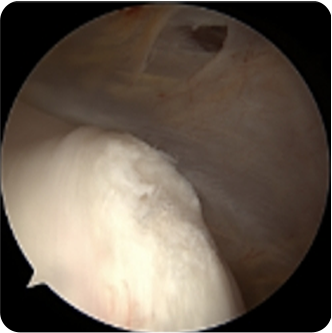

회전근개파열의 여러 모습들

기존의 삼각근을 절개하고 회전근개를 노출시켜서 수술하는 방법이 아닌 초소형 카메라인 관절내시경을 삼각근을 통과시켜 회전근개파열을 봉합합니다. 힘줄 주변의 근육 손상을 최소화시킬수 있기 때문에 수술 후 유착 반응이나 통증 반응이 감소하여 빠른 재활이 가능합니다.